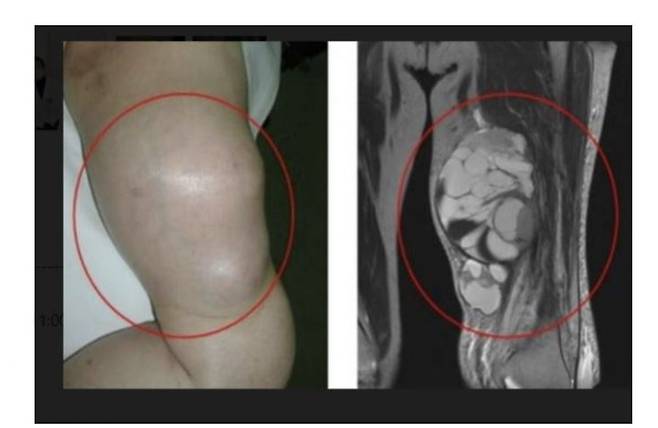

연부조직 육종은 근육, 지방, 혈관 등 골격을 제외한 조직에서 발생하는 악성 종양이다. 팔, 다리, 복부 내 등 인체 어느 부위에서나 발생할 수 있다. 양성 종양(지방종 등)과 달리 암이므로 조기 진단과 적절한 치료가 매우 중요하다.